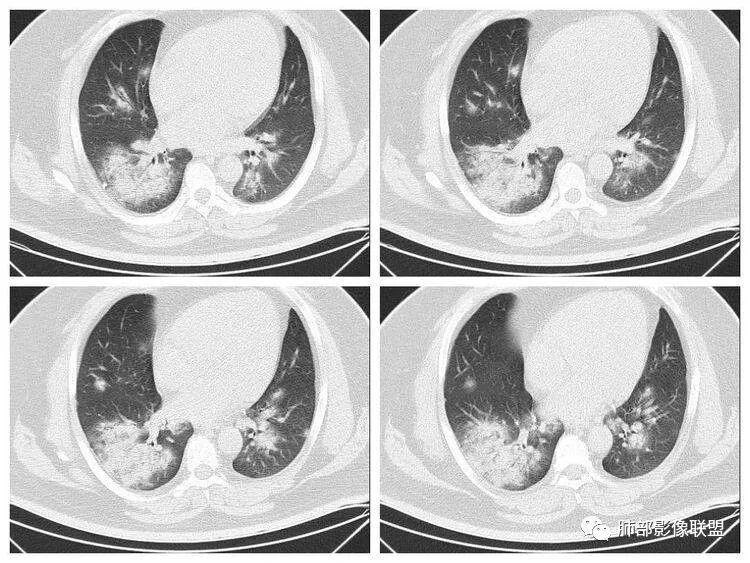

青年男性、急性病史、发热、咳嗽、常规抗炎无效病灶沿支气管血管束分布  GGO+实变边界模糊部分沿胸膜下分布哪几种可能?

南边:1、感染:间质分布——病毒、支原体,支原体一般树芽征明显,累及小气道多,而且临床轻,不太支持2、血管炎,需要相关病史3、肺水肿:心脏不大,无胸水、无中央间质增厚、小叶间隔增厚,不太支持4、PAP,病史影像表现都不支持初学者:可能是病毒,但是好像并不是我们常见的流感病毒实变为主,腺病毒?就是太多灶了一点

重症流感的定义出现以下情况之一者为重症病例1.持续高热>3天,伴有剧烈咳嗽,咳脓痰、血痰,或胸痛2.呼吸频率快,呼吸困难,口唇紫绀;3.神志改変:反应迟钝、嗜睡、躁动、惊厥等4.严重呕吐、腹泻,出现脱水表现;5.合并肺炎6.原有基础疾病明显加重。危重症流感的定义出现以下情况之一者为危重病例1.呼吸衰竭2.急性坏死性脑病3.脓毒性休克4.多脏器功能不全5.出现其他需进行监护治疗的严重临床情况。重症流感病毒肺炎的肺部影像以双肺多发磨玻璃影及实变影为主要表现,可合并少量胸腔积液,典型的H1N1双肺外带分布为主。随病程发展,部分患者出现实变及纤维化临床表现早期流感样症状:咳嗽、咳痰、发热、咽痛、全身酸痛。主要临床表现:肺炎、ARDS。患者咳嗽、咳痰、呼吸困难、氧饱和度低,发热、咽痛、全身酸痛,神志异常。甚至呼吸衰竭、休克,多器官衰竭等等。相关链接https://m.qlchat.com/topic/details?topicId=280000451285864

起病突然,高热,双肺多发磨玻璃影及实变影,胸膜下分布为主,不具有肺门分布优势,也没有小叶间隔增厚,一般会首先考虑病毒感染,尤其是甲流。